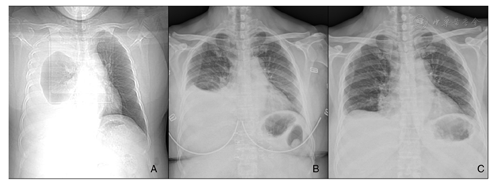

患者徐某,女,51岁,因"发现肾功能异常4年,规律腹膜透析1年,间断胸闷、气短3个月,加重7d"于2017年10月16日入院。患者于4年前发现血肌酐升高,1年前确诊为"慢性肾脏病5期",于2016年9月14日行腹膜透析置管术后行连续性非卧床腹膜透析(continuous ambulatory peritoneal dialysis,CAPD)治疗,具体腹膜透析方案为:1.5%腹透液2 000 ml留腹,4次/d,总超滤量约1 000 ml/d,尿量约1 200 ml/d。于2017年7月无明显诱因出现胸闷气短,平卧时加重,每日总超滤量为负值,尿量约1000 ml/d,就诊于我院,给予加强腹膜透析后,上述症状好转。于2017年10月9日再出现胸闷、气短症状,伴咳嗽,无咳痰,夜间不能平卧。入院后体格检查:体温:36.5℃,脉搏:80次/min,呼吸:18次/min,血压:160/90 mmHg(1 mmHg=0.133 kPa)。右侧下肺区叩诊浊音,呼吸音减弱,语音震颤减弱。心界正常,心率80次/min,律齐,未闻及杂音。腹部略膨隆,无压痛、反跳痛,肝脾肋下未触及,移动性浊音阳性。腹膜透析管外口成型良好。双下肢轻度水肿。辅助检查:血白蛋白41.0 g/L,血肌酐916.0 μmol/L,血红蛋白109 g/L,腹水常规:黄色,李凡他试验阴性,白细胞总数4×106/L,胸水生化:总蛋白0.70 g/L,乳酸脱氢酶3.00 U/L,葡萄糖29.64 mmol/L,氯96.20 mmol/L,腺苷脱氨酶0.91 U/L。胸部CT示右侧胸腔可见大量液性低密度影,肺组织受压(图1A)。因为胸腔积液中葡萄糖的含量较高,"胸腹瘘"可能大。给予腹透液中加入2 ml美兰,灌入腹腔,平卧2 h后,经胸腔引流出淡蓝色胸水。明确诊断为腹膜透析相关性胸腹瘘。因患者拒绝手术治疗或转为血液透析过渡治疗,未进一步检查明确瘘口位置。胸腔穿刺引流后胸闷气短症状较前好转,将腹膜透析方案改为IPD:2.5%腹膜透析液,1 000 ml/次,8次/d,留腹1.5 h/次,夜间干腹,总超滤量约450 ml/d,尿量1500 ml/d。治疗1个月后复查胸部X线胸腔积液量明显减少(图1B),治疗6个月后复查胸部X线:右肺未见异常(图1C)。

注:IPD:间断性腹膜透析;A:治疗前,大量胸腔积液;B:IPD治疗1个月后,胸腔积液明显较少;C:IPD治疗6个月后,胸腔积液完全消失